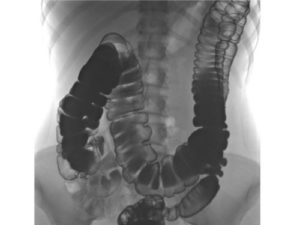

При появлении симптомов опущения кишечника необходимо обратиться к гастроэнтерологу для основательного обследования. Главным диагностическим методом выявления патологии является ирригоскопия.

Процедура подразумевает введение в кишку контрастного вещества с помощью клизмы и проведение рентгена кишечника. В ходе обследования врач определяет масштабы патологии, особенности расположения кишки.

- ирригоскопия – рентгенологическое исследование кишечника с введением контраста – наиболее информативный метод диагностики; позволяет определить градус опускания органа;